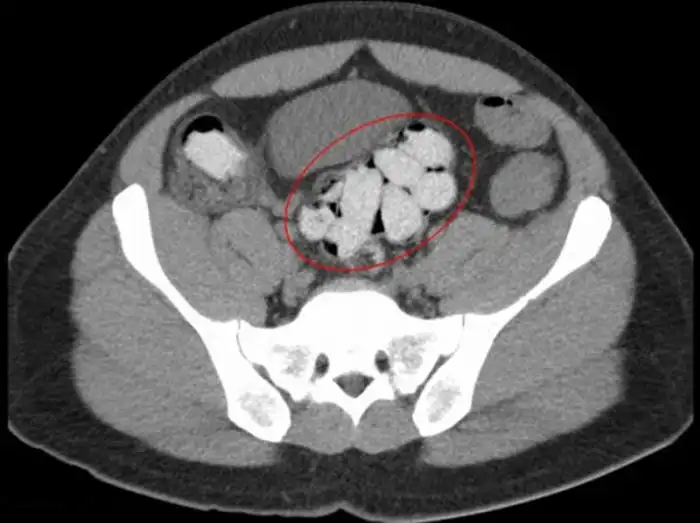

20 контейнеров с наркотиками в толстой кишке

Наркотики в толстой кишке